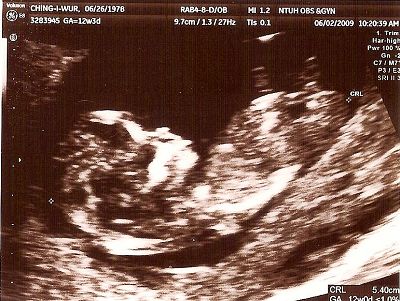

6月10日

到了看報告的日子

整體指數正常,但我還是很擔心

要求醫生再幫我照一次,但仍然還是不明顯

醫生說因為指數很低,且我還年輕,所以沒關係

且有百分之三十的正常寶寶也有此情況

叫我放寬心別多想